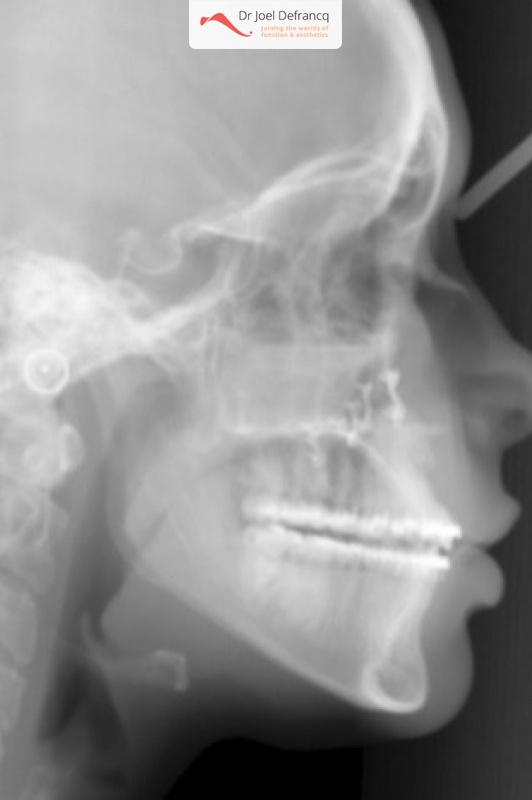

Daphne: Open beet

Diagnose van het gezicht

- Te lange bovenkaak

- Open beet

Dentale diagnose

- Klasse I

Kaakchirurgie

- Verlenging bovenkaak (Le Fort I)